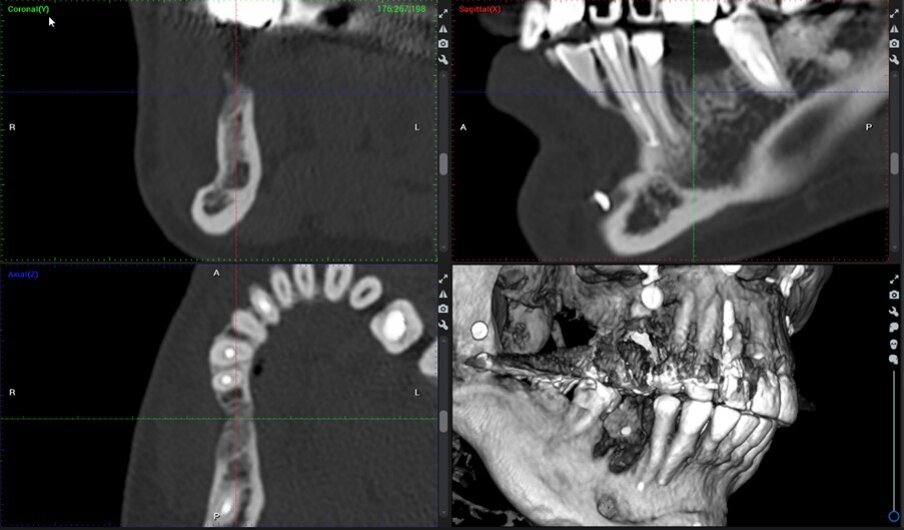

Una paziente di 68 anni di sesso femminile ha frequentato la nostra clinica e ha richiesto un trattamento di riabilitazione per il sito edentulo 46. La paziente era una non fumatrice in buona salute, senza malattie parodontali attive (nessuna perdita di attacco, tasche al sondaggio e BOP). È stata eseguita una tomografia computerizzata a fascio conico (CBCT) preoperatoria nel quarto quadrante inferiore (Fig. 16). I risultati hanno rivelato un’atrofia orizzontale della cresta nella zona del sito 46. La densità ossea è stata definita come di tipo 2 e la distanza dal margine alveolare più coronale al canale alveolare inferiore era sufficiente per posizionare un impianto dentale di 10 mm di lunghezza. Durante l’esame clinico è stata misurata una ampiezza del tessuto cheratinizzato di 4 mm sulla sottile cresta.

Fig. 16_Immagini CBCT preoperatorie del sito 46.

Rivalutazione radiologica

La stessa metodologia del caso 1 è stata applicata per il confronto T1-T2-T3. La valutazione è stata effettuata attraverso sezioni trasversali prese nel mezzo del sito sulla sezione assiale e perpendicolari alla cresta alveolare (Figg. 28, 29).

Fig. 29_Valutazione CBCT del caso 2 da sinistra a destra: a) immagini coronali e assiali preoperatorie; b) immagini coronali e assiali CBCT post-operatorie a 4 mesi; c) immagini coronali e assiali CBCT a 2 anni e 7 mesi.